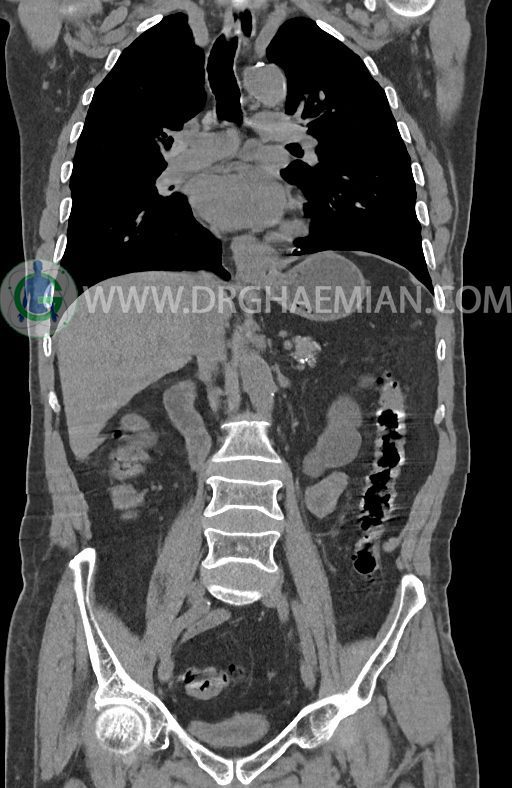

در سی تی اسکن اسپیرال ریه ها و مدیاستن، شکم و لگن با و بدون کنتراست وریدی (مولتی دیدکتور 16 با مقاطع ظریف و بازسازی کرونال) :

–افزایش ضخامت تومورال دیستال مری و GEJ در سگمانی به طول 4cm-5cm (T2 or T3)

–توده هیپودنس به قطر 10mm در پارانشیم طحال مشهود است. Quadriphasic MRI پیشنهاد می گردد.

–کیست های کورتیکال متعدد هر دو کلیه به بزرگترین قطر 56mm

–پروستات به دیامتر عرضی بزرگ حاوی فوکوس کلسیفیه